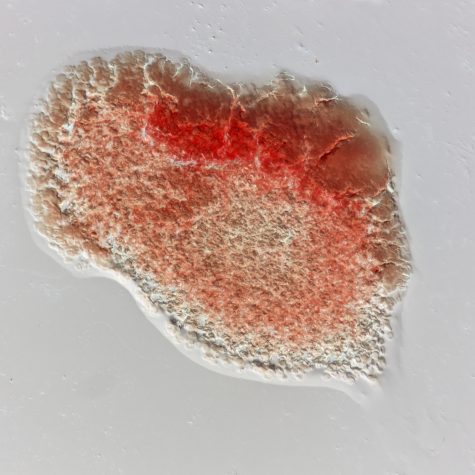

A thrombus, colloquially called a blood clot, is the final product of the blood coagulationstep in hemostasis. There are two components to a thrombus: aggregated platelets and red blood cells that form a plug, and a mesh of cross-linked fibrin protein. The substance making up a thrombus is sometimes called cruor. A thrombus is a healthy response to injury intended to prevent bleeding, but can be harmful in thrombosis, when clots obstruct blood flow through healthy blood vessels.

A thrombus, colloquially called a blood clot, is the final product of the blood coagulationstep in hemostasis. There are two components to a thrombus: aggregated platelets and red blood cells that form a plug, and a mesh of cross-linked fibrin protein. The substance making up a thrombus is sometimes called cruor. A thrombus is a healthy response to injury intended to prevent bleeding, but can be harmful in thrombosis, when clots obstruct blood flow through healthy blood vessels.